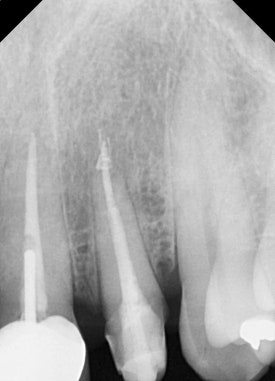

교정적/외과적 정출술을 시행하기 앞서

치아 상태에 대한 면밀한 조사가 필요합니다.

-

심각한 치아 염증이 없어야 합니다.

뿌리의 길이가 충분히 길어서, 치아를 밀어올리더라도 뼈 안에서 전체 치아를 지지해줄 충분한 길이가 남아있어야 합니다.

이 두 가지 조건을 충족시켜야

비로소 정출술을 시도할 수 있습니다.